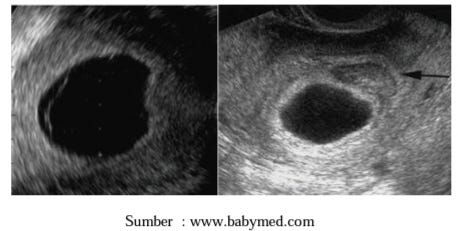

Gambar Usg Kehamilan Kosong